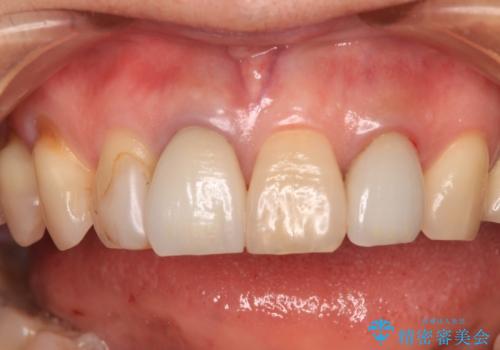

- 詰め物やクラウンで色合いが異なっている上顎前歯を気にして来院された患者様です。

長さや形を左右対称に整えたいとのことで、4歯をオールセラミッククラウンにて補綴治療を行うこととしました。